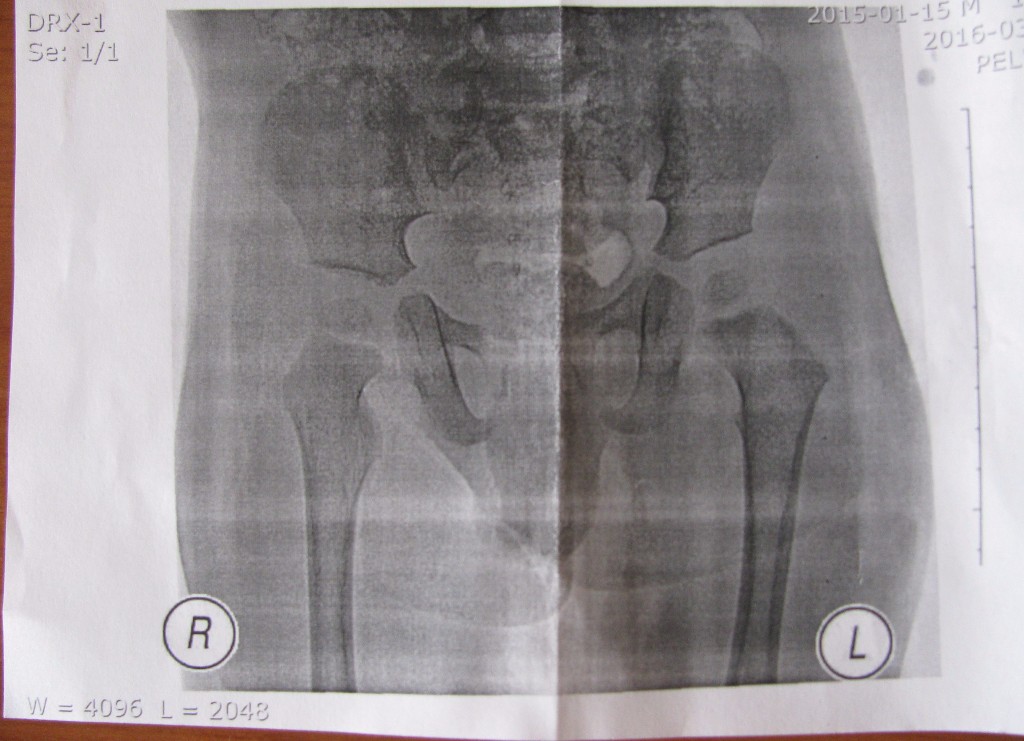

Рентгенодиагностика При подозрении на врожденный вывих бедра обязательно проводится рентгенография тазобедренных суставов. Схема оценки тазобедренных суставов по рентгенограмме представлена ниже.

Пример оперативного лечения вывиха бедра и отдаленный результат.

Объективным методом диагностики дисплазии является рентгенография тазобедренных суставов.

рентгенографией в 3 мес. - Оценка рентгенограмм ни в коем случае не

должна проводиться «на глазок», а только

инструментально – при помощи транспортира и линейки. Снимок должен быть обязательно «расчерчен» с измерением специальных параметров. Именно по ним ставится

диагноз или же принимается решение о прекращении лечения.